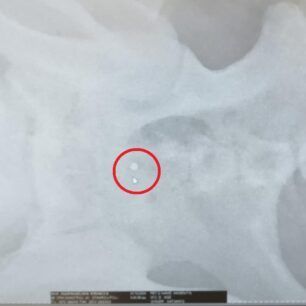

Τελικά οι ακτινογραφίες έδειξαν τι έχει συμβεί. Ο σκύλος είναι πυροβολημένο. Δεκάδες σκάγια εντοπίστηκαν στο σώμα του, στην σπονδυλική στήλη με αποτέλεσμα το ζώο να μην μπορεί όχι μόνο να κινηθεί αλλά και να αφοδεύσει με αποτέλεσμα στο έντερο να έχουν συσσωρευθεί κόπρανα.

Η Ευτυχία Πουρνάρα με αφορμή το περιστατικό επισήμανε τα εξής στις 3 Ιανουαρίου: «ΦΙΛΟΙ ΜΟΥ ΒΟΗΘΗΣΤΕ ΑΥΤΟ ΤΟ ΠΛΑΣΜΑ ΝΑ ΓΙΝΕΙ ΚΑΛΑ ΓΙΑΤΙ ΕΝΩ ΜΟΥ ΕΙΠΑΝ ΠΡΕΠΕΙ ΝΑ ΤΟ ΧΤΥΠΗΣΕ ΑΥΤΟΚΙΝΗΤΟ  ΣΥΓΚΛΟΝΙΣΤΙΚΑ ΟΤΑΝ ΟΙ ΑΚΤΙΝΟΓΡΑΦΙΕΣ ΔΕΙΞΑΝ ΟΤΙ ΤΟ ΚΟΡΜΑΚΙ ΤΟΥ ΣΚΥΛΑΚΟΥ ΕΙΤΑΝ ΓΕΜΑΤΟ ΣΚΑΓΙΑ ΔΙΑΣΠΟΡΑΣ ΕΝΑ ΤΟ ΒΡΕΙΚΕ ΣΤΗΝ ΣΠΟΝΔΥΛΙΚΗ ΣΤΥΛΗ Ο ΓΙΑΤΡΟΣ ΜΟΥ ΚΥΡΙΟΣ ΚΑΡΑΜΗΤΡΟΣ ΜΟΥ ΕΔΩΣΕ ΑΓΩΓΗ  ΤΟ ΖΩΟ ΔΕΝ ΜΠΟΡΟΥΣΕ ΝΑ ΑΦΟΔΕΥΣΗ ΚΑΙ ΠΡΙΣΤΗΚΕ ΚΑΝΟΥΜΕ ΑΓΩΝΑ ΝΑ ΤΟ ΒΟΗΘΗΣΟΥΜΕ ΤΟ ΚΑΛΟ ΕΙΝΑΙ ΟΤΙ ΑΙΣΘΑΝΕΤΑΙ ΤΑ ΠΟΔΑΡΑΚΙΑ ΤΟΥ ΘΑ ΣΑΣ ΠΩ ΝΕΟΤΕΡΑ ΤΟ ΚΑΘΑΡΜΑ ΠΟΥ ΤΟ ΠΥΡΟΒΟΛΗΣΕ  ΕΥΧΩΜΕ ΑΥΤΟ ΠΟΥ ΕΚΑΝΕ ΝΑ ΤΟ ΒΡΕΙ ΜΠΡΟΣΤΑ ΤΟΥ ΜΗΝ ΞΕΧΝΑΤΕ ΒΟΗΘΗΣΤΕ  ΕΧΩ ΑΓΩΝΑ ΜΠΡΟΣΤΑ ΜΟΥ ΓΙΑ ΝΑ ΣΩΘΕΙ ΣΤΕΙΛΤΕ ΜΗΝΝΥΜΑ ΣΤΟ ΜΕΣΣΕΝΤΖΕΡ  ΕΥΧΑΡΙΣΤΩ ΠΟΛΥ ΤΗΛ 6946348888 ΚΙΛΚΙΣ».